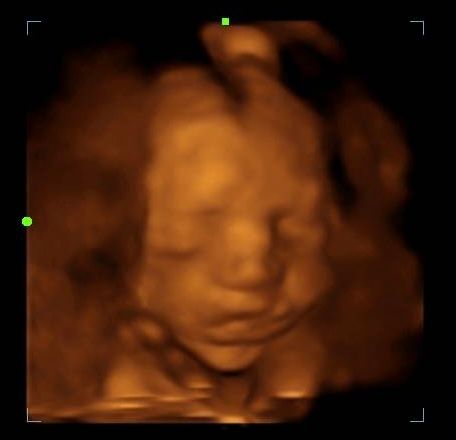

2d, 3d,4d & HD live

Enjoy a private, affordable ultrasound from the comfort of your home, perfect for moms between 7–41 weeks. Share the moment with loved ones by connecting directly to your TV for real-time viewing in 2D, 3D, or 4D. Ideal for baby showers or gender reveal parties!